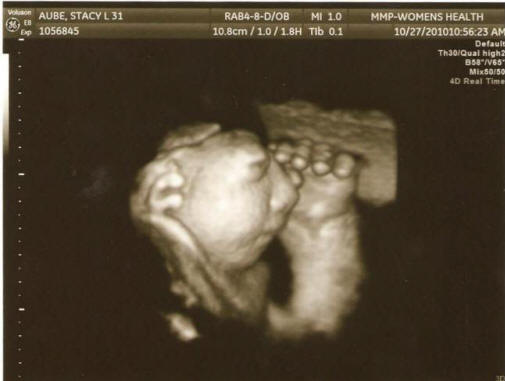

Fotók a nyílt forrásból a 27 országból a terhes nők orvosi feljegyzései során a szakértők megragadtak az anatómiai klinikákon nyilvántartott területek, ahol azt vizsgálják dolgoztak, mint betegek, ivtak alkoholt, drogokat vagy füstölt termékek, milyen területen éltek és honnan a forrás ivott vizet. Végül is kormánytisztviselők arra a következtetésre jutottak, hogy nem tudták kitalálni a „feltételeket vagy okokat” ennek a jelenségnek. “Az eredmények csalódást okoztak, de nem igazán váratlan, beismert Jim Kucik (Jim Kucik) tudós, aki részt vett a tanulmányban. – Általában az ilyen születési rendellenességek okozzák a tényezők kombinációja, amelyet nagyon nehéz felismerni. nem lehetséges, hogy mindez csak véletlen egybeesés. ” És itt van a genetika Susie Ball tanácsadó úgy véli, hogy három megyében Washington államban van néhány probléma, amelyet fel kell venni fokozott figyelmet kell fordítani a nők jövőbeni védelme érdekében fogamzóképes korú. Vigyázat, sokkoló fénykép.

Fotó nyílt forrásból “Nem szeretném megijeszteni az embereket, de az, ami történik, riasztó engem ”- hangsúlyozta. – fogadva az orvosi személyzet adatait széles körben nyilvánosságra kell hozni, hogy a fogamzóképes nők minden szükséges intézkedést megtegyenek a következők érdekében: megakadályozzák e patológia kialakulását. Először azt tanácsolom nekik vegyen folsavat. ” A tudósok már elolvasták az eredményeket a potenciális tényezőket azonosító korábbi tanulmányok anencephaly kialakulásának kockázata: alacsony étrendi folát savak, növényvédő szereknek való kitettség és az ivóvízszennyezés nitrátok.